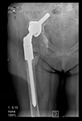

The guiding wire was inserted and controlled with fluoroscopy flashes (Figure 4). The drilling and reaming were carried out in accordance with the recommendations:

Figure 4.

The biocompatible aiming device after insertion of the guiding wire.

In all the cases operated with the above-described targeting procedure, the stems of the cups remained between the cortical bone surfaces without perforation of the linea terminalis, as shown by postoperative radiographs. There were no complicated surgical situations. In 16 cases, the wound healings were uneventful, and the hips were able to bear weight again after postoperative rehabilitation.